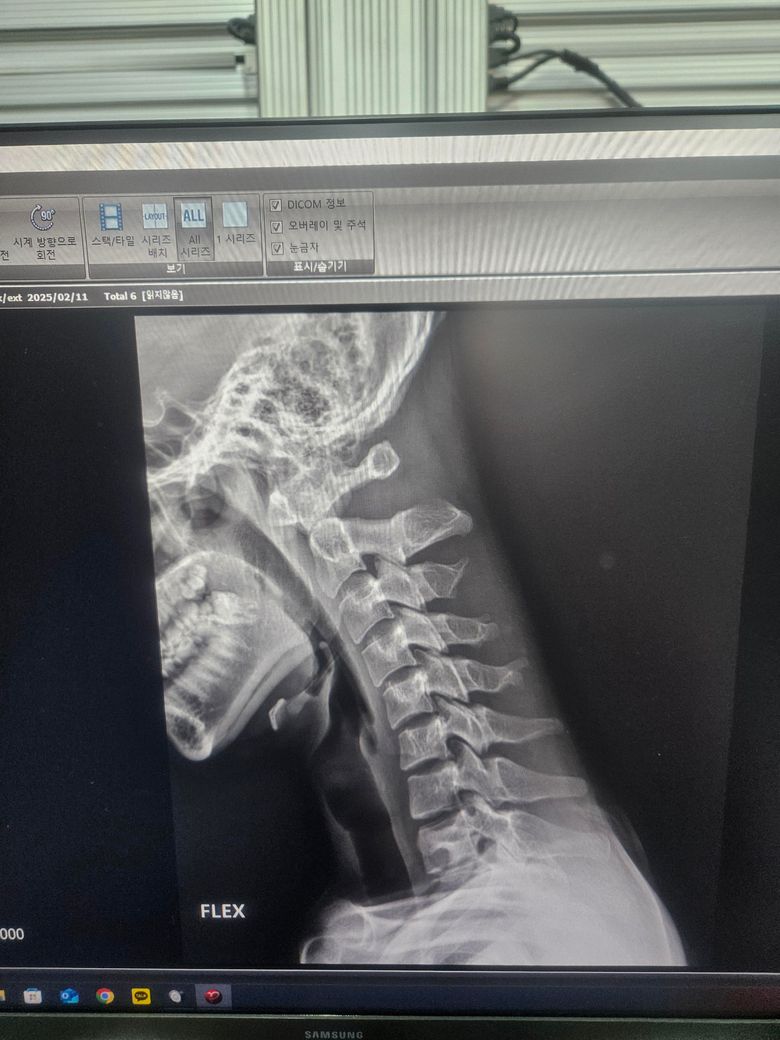

경추 불안정증인가요? 자세히 봐주세요 경추 1번 2번

경추 1번 2번 굴곡 신전시 이상이 있나요 제가 볼땐 많이 떨어지는것 같은데 다 아니라고 하시네요 전문의 답변 기다립니다 부탁드려요

• 2번 째 사진

올려주신 엑스레이 사진에서 특별한 이상 소견은 저명하지 않습니다.